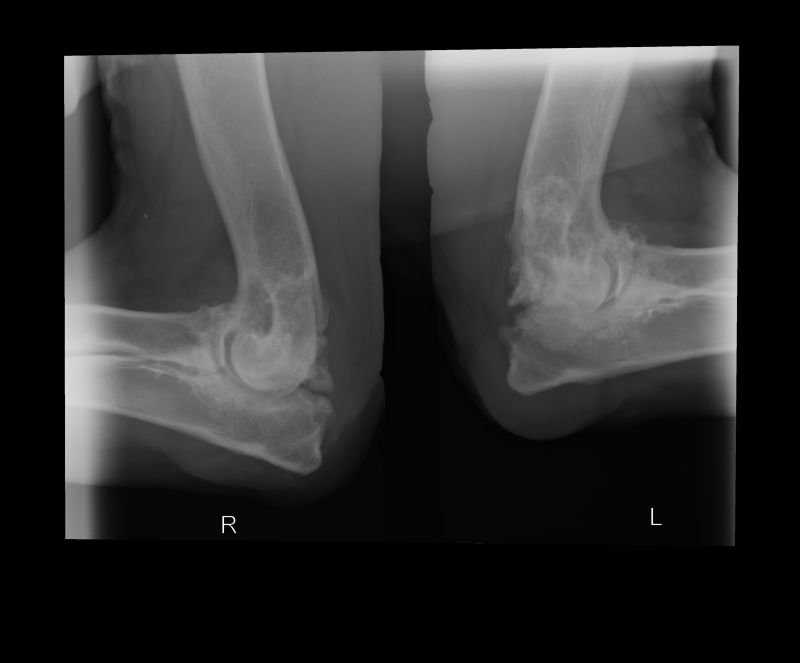

Abnormal Pathology on your pet

Shown on x-ray images which we have taken over the years.

Some interesting patient cases